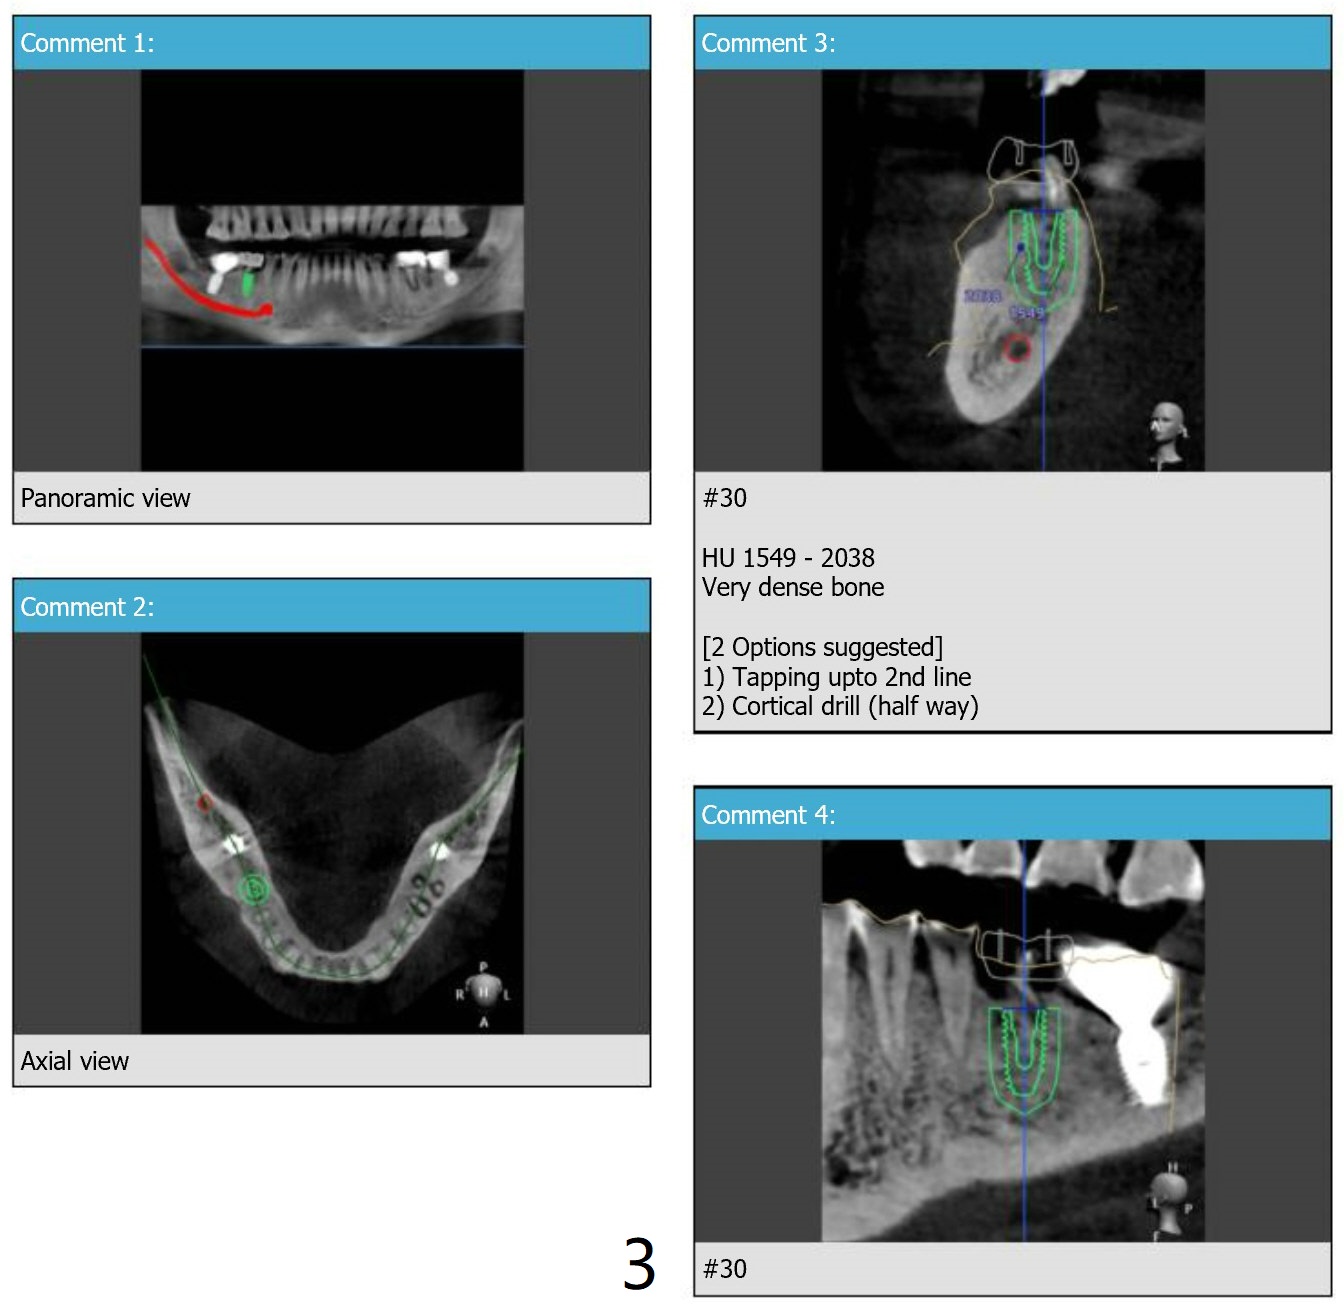

Cortical

Drill for Hard Bone

When bone density is high, a cortical drill in stead of cortical tap is used prior to implant placement.